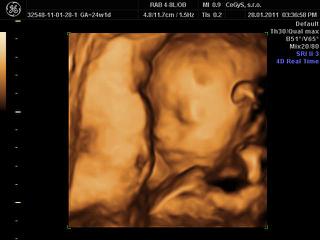

ahojte, my sme dnes boli na 3D, takže sme plní zážitkov 😀

no, princeznička je to na 100 percent 😎 😎 😎 veľmi sa tešíme. Na začiatku sa nám ukazovala pekne, potom už sme ju asi otravovali tak sa zabárala noštekom do placenty a nechcela sa ukázať.. ale máme asi 10 videosekvencií a 10 fotiek takže super!!!!

@alena24 no spolupracovala prvych 10 minut potom sme ju len tahali zo strsny na stranu, opica jedna, ale stihli sme to na zaciatku ponahravat, sme sa poucili z morf.uzv, tam sa nam tiez schovavala!!! Ano aj nas meral, zodpovedame presne tt, cize 24,4 tt a vazime 670 g. Aj nam ukazoval nejaky graf k tomu a ideme pekne stredom, co je priemer tak ako ma byt.